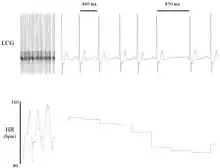

Heart rate variability (HRV) is the physiological phenomenon of variation in the time interval between heartbeats. It is measured by the variation in the beat-to-beat interval.

Other terms used include "cycle length variability", "R–R variability" (where R is a point corresponding to the peak of the QRS complex of the ECG wave; and RR is the interval between successive Rs), and "heart period variability".